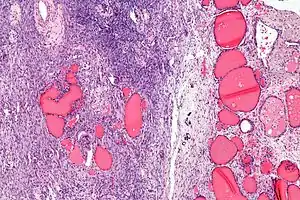

Struma ovarii é um tumor do ovário, geralmente benigno e unilateral. Ele é uma variante de teratoma maduro, composta por mais de 50% de tecido tireoideano maduro. Corresponde a cerca de 1% de todos tumores de ovário e 2,7% dos teratomas maduros.